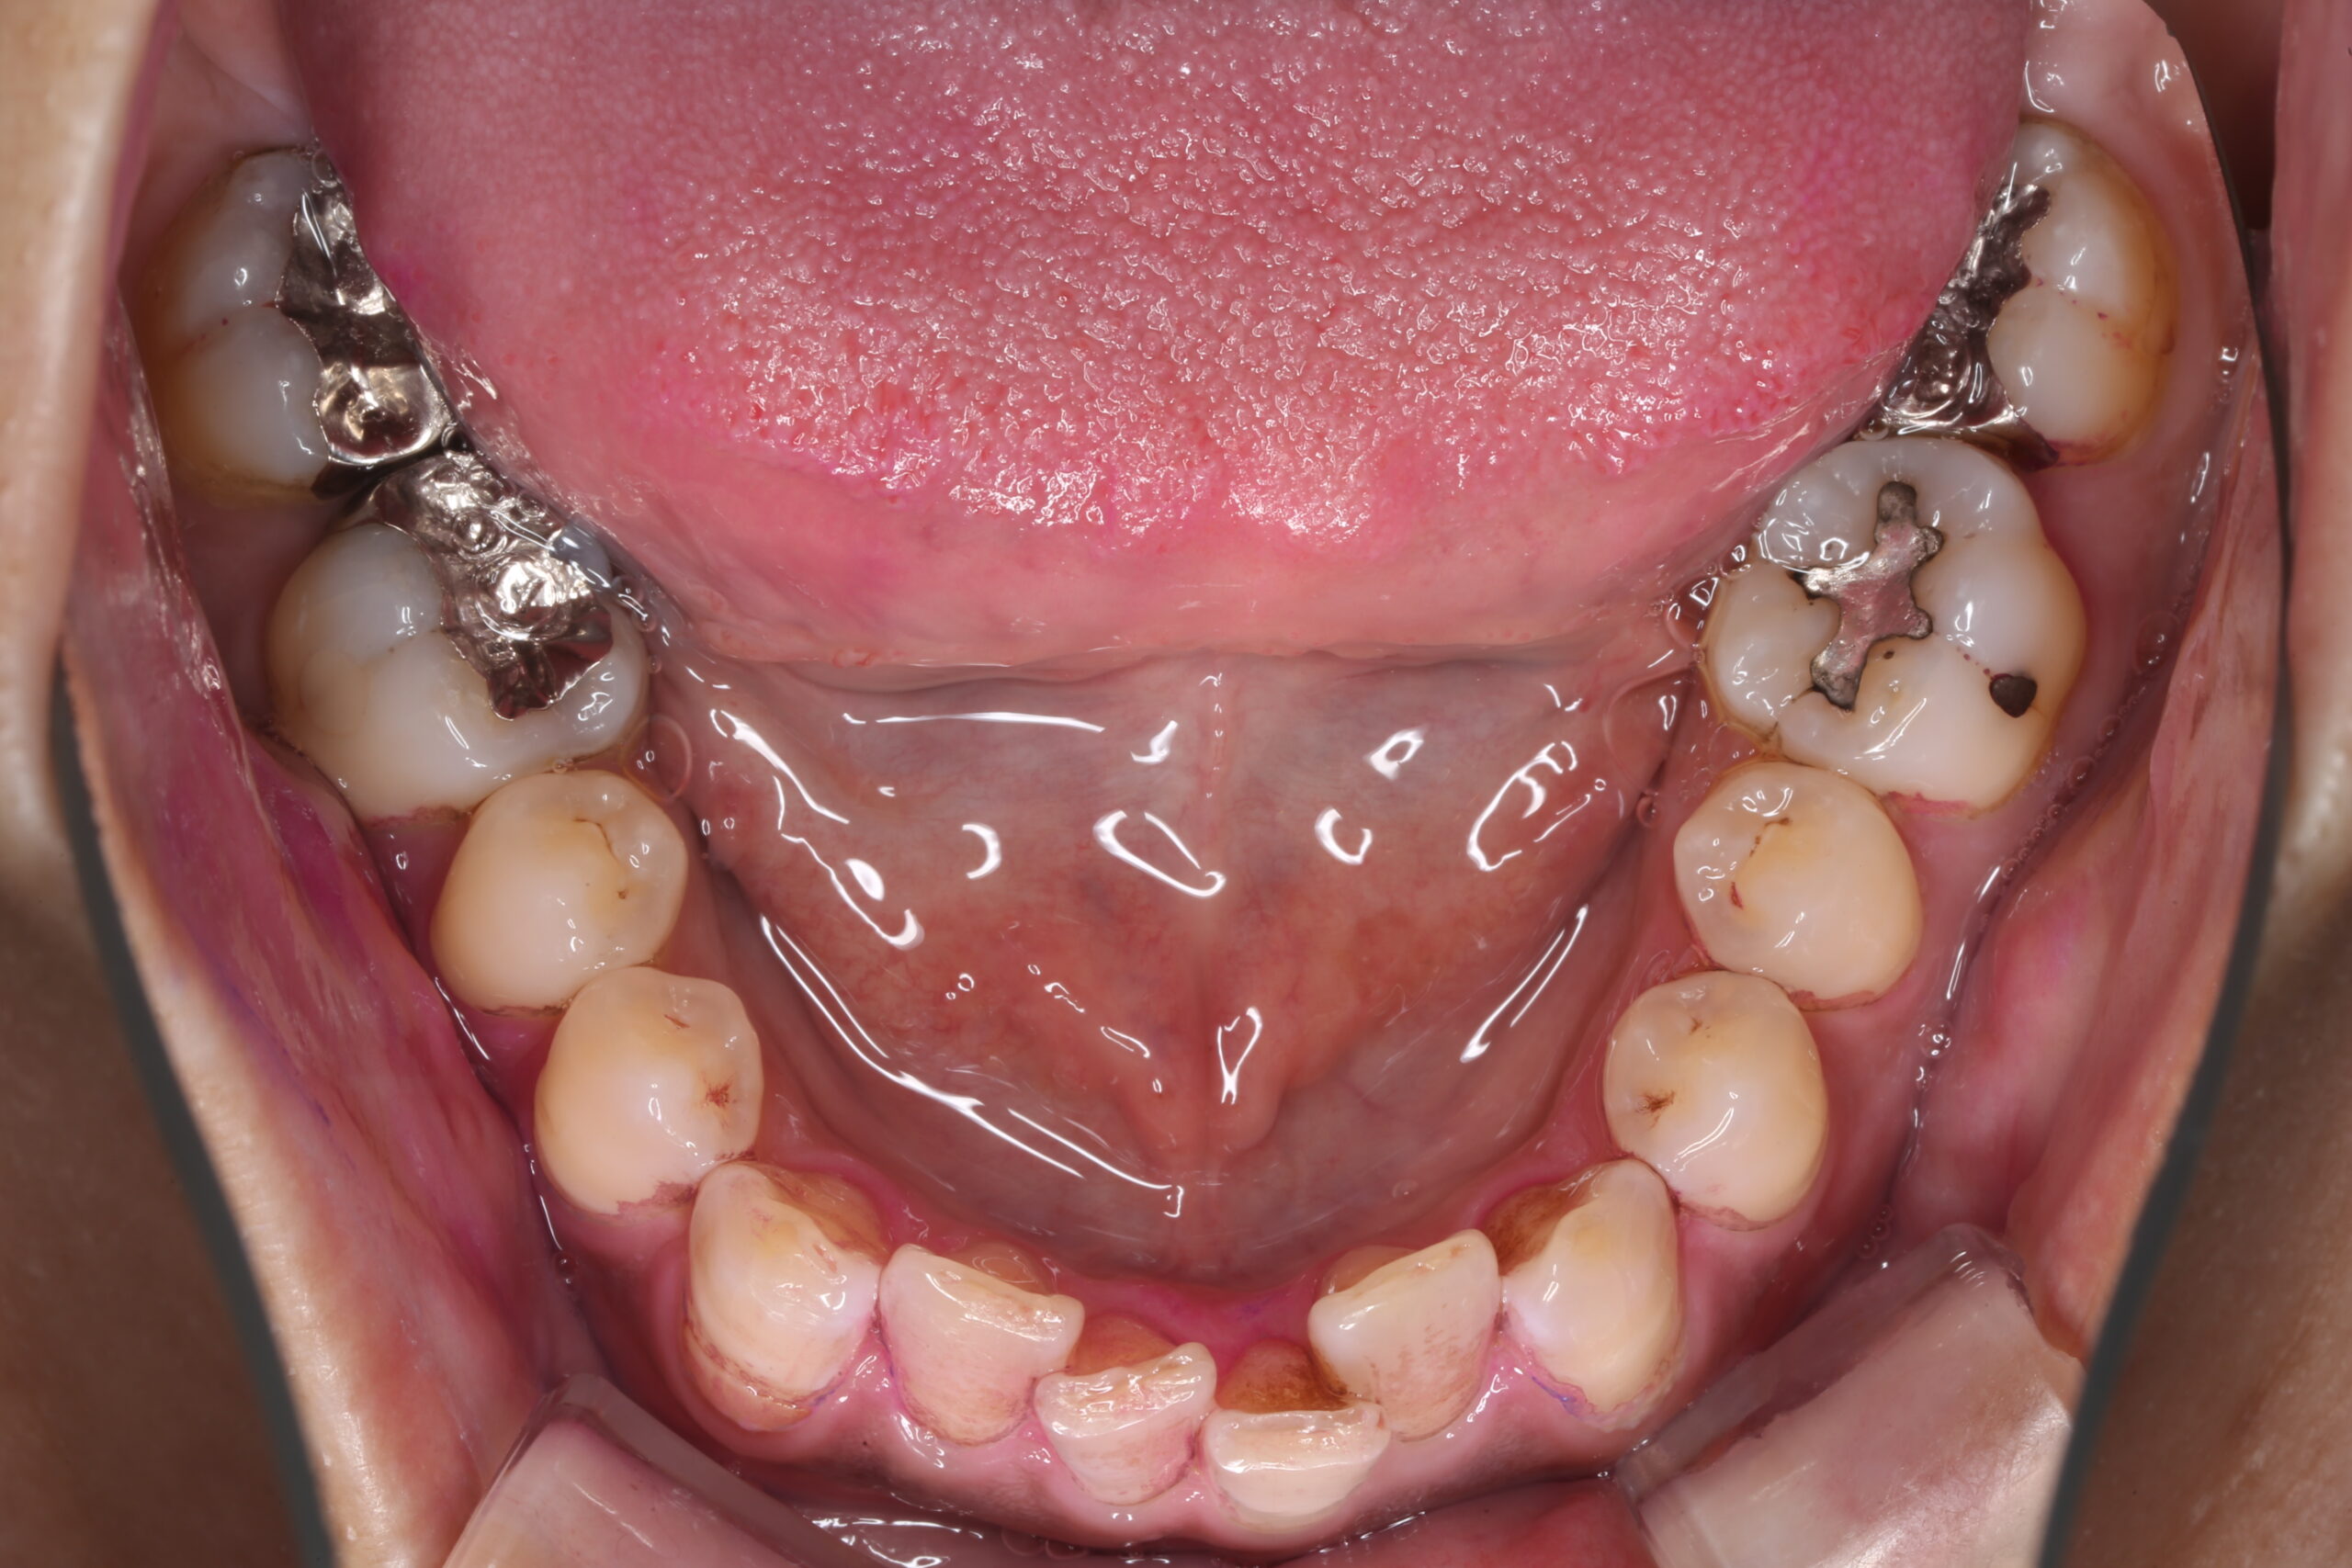

上下の奥歯の関係は悪くありませんでしたが、下の前歯の叢生(がたつき)が良くありませんでした。

下の前歯に叢生があると噛み合わせが作りにくく、最終的な修復物の寿命が短くなることが多いため、矯正治療で歯並びを整えることになりました。

期間の制限もあり、完全に、とは言えませんが整えることができました。

これにより上の前歯の修復の難易度が大きく下がり、また歯の寿命も長くなります。